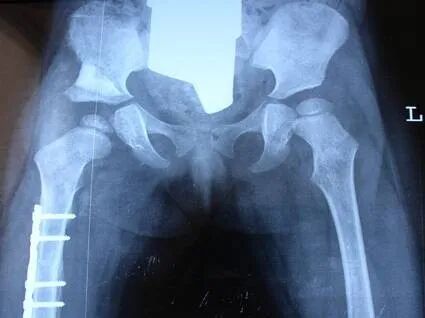

发育性髋关节脱位

6.jpg